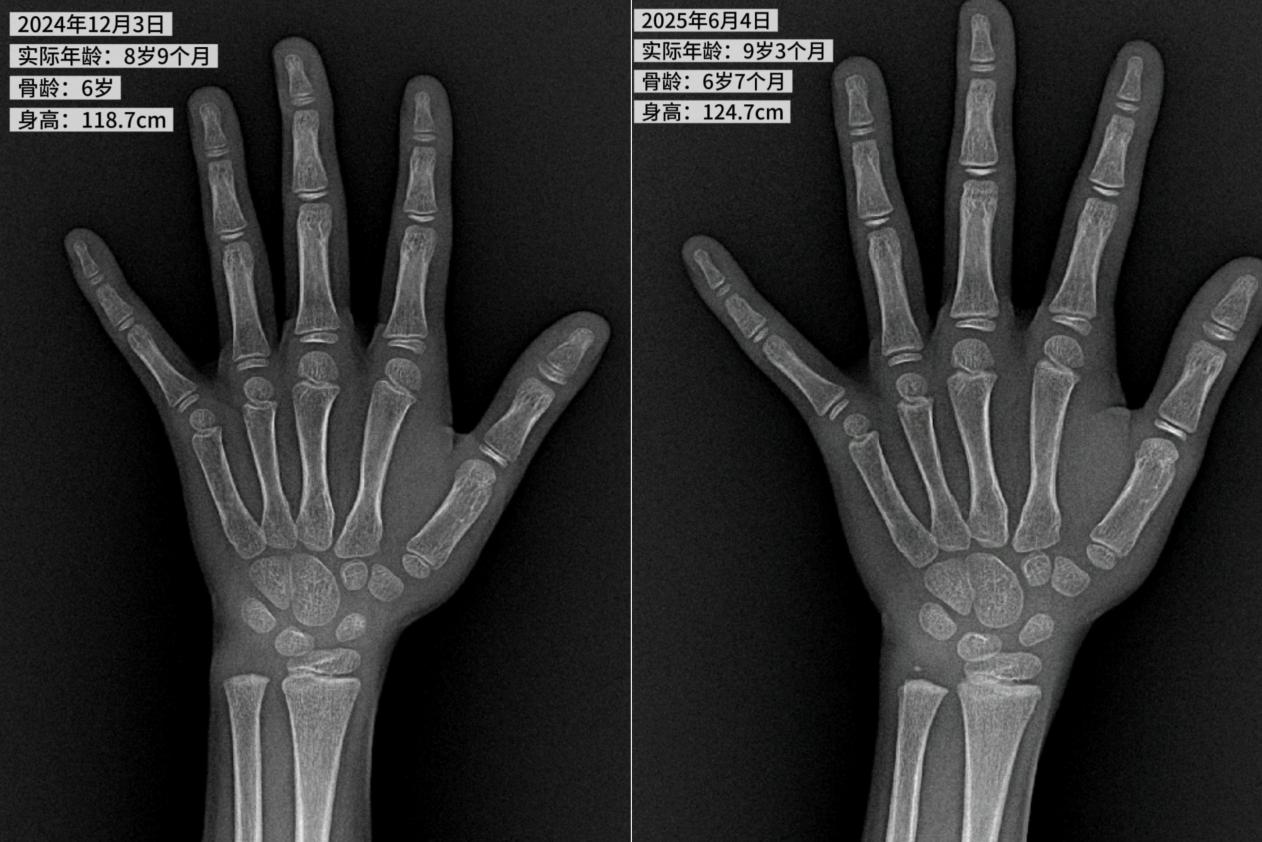

通过测量,彤彤目前的身高为 118.7 cm,小于 8 岁 9 月女孩身高的第 3 百分位 122.2 cm,比同龄女孩的平均身高 132.7 cm 足足矮了 14 cm,已经达到矮小诊断标准。另外,通过问诊发现,彤彤是足月出生,出生体重 4.0 kg,既往没有特殊疾病史;爸爸 180 cm,妈妈 163 cm,根据计算彤彤的遗传身高是 165±5 cm,但根据彤彤目前的生长趋势显然无法达到遗传身高。在给彤彤完善了矮小相关检查后发现,8 岁 9 个月的彤彤骨龄只有 6 岁,胰岛素样生长因子低于正常水平,生长激素峰值为 6.599ug/l,其他相关检查无异常,排除了小于胎龄、慢性系统性疾病、甲状腺功能减低等疾病,最终被诊断为「生长激素缺乏症」。

通过和刘医生的充分沟通交流后,彤彤爸爸妈妈一致决定给孩子立即投入治疗。刘医生按照儿童矮小诊治规范,建议采用生长激素治疗为主,辅以饮食调整、保障睡眠及运动干预。可喜的是,经过 6 个月的治疗,彤彤再次来院复查时骨龄为 6 岁 7 月,身高共增长了 6 cm,达到 124.7 cm,相当于治疗前 2 年的身高增长速度。